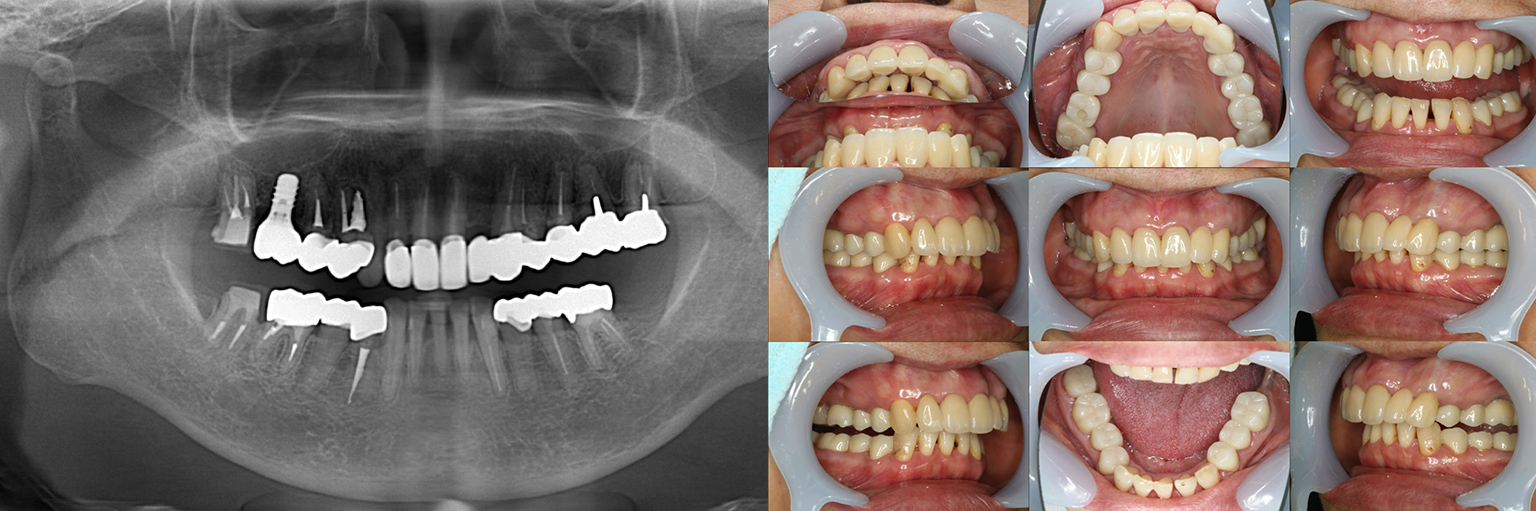

【治療例 3】奥歯が痛い、全体的にみて欲しい 60歳

今まで何回歯を入れてもトラブルが起きるために、奥の歯を入れないまま今日に至る、ということでした。

噛み合わせ・骨格を読み解き、今後の人生でトラブルが起きにくいように全体的な治療計画を練りました。 - 治療費用・方針

骨格の前後的な差がある方でした。術前のレントゲンより、上下で歯牙の損傷に明らかな差があるのがみてとれます。

上の歯がないところにインプラント治療を行い、上顎は全てインプラントフィクスチャーによる固定性の歯を入れられることも費用的には可能な方でした。

しかし、治療において重要なのは今目の前の歯を見ることではなく、なぜ目の前の歯になったかを考え、未来へ活かすことです。

骨格的な前後差を考慮することなく歯をいれても、装着した人工物は決して長持ちしません。

今回の症例では、敢えて上顎は総義歯形態をとり、骨格的な前後の差を解消するよう工夫しました。

上顎の残っていた歯も、差し歯としては使えずとも、敢えて根だけ残すことによって組織を温存し、義歯の安定に寄与するよう設計しました。

ここまで全体的にしっかり治療しておけば、今後の人生においてトラブルになるようなことにはならないでしょう。 - 治療のリスク

上顎の総義歯は、馬蹄形という上顎の覆う部分が小さいタイプで作成いたしました。強度に劣るため、割れる可能性があります。

下顎のクラウン・ブリッジは、丁寧な形成・印象処置と自費専門の技工士によって製作されたもので、虫歯による損傷が今後起こりにくいとは考えますが、定期的なメンテナンスは必須であり、生涯もつものではありません。

神経のない歯(失活歯)は神経がある歯に比べて力が大きくかかりやすく、根が割れたりするリスクがあります。割れ方にもよりますが、基本的には歯が割れてしまうと抜歯処置を行わなければならないことがほとんどです。

【治療例 4】左上のインプラントがとれた 歯が欠けて困っている 79歳

他院で治療を行ったインプラントの歯が取れたということでいらっしゃいました。

また、あちこちの被せ物が欠け、困っているとのことでした。 - 治療費用・方針

既にインプラント治療がなされており、使えるインプラントを使いながら足りないところにインプラントフィクスチャーを埋入し、噛み合わせを再構築する必要がある方でした。

上の前歯、右上の奥歯のインプラントはもう既に使える状態ではなく、また年月を経てすり減ってしまった下の前歯は噛み合わせを再構築する上で利用が難しい状況でした。

年齢を考えると、今回の治療で歯科治療を終えてしまい、残りの人生においてはメンテナンスのみで歯科へ通う状況を作りきってしまうことが求められました。

以上より、潔く残っている歯牙は抜去させていただき、上下をインプラントフィクスチャーによって固定式の歯を入れることとしました。 - 治療のリスク

レントゲンをよく見るとお分かりいただけるかと思いますが右下の奥歯のインプラント(レントゲンでは左右逆にうつるので、左下)が既にインプラント周囲炎になっていました。

本当に治療をやり切ってしまうなら、右下の奥2本のインプラントを抜去、新しいインプラントフィクスチャーを埋入すべき症例でした。

しかし、患者さんとの話し合いで、「まだ使えるインプラントは置いておこう」ということになり、右下のインプラントは置いたまま治療を行っています。今後の人生の中で腫れたり痛む可能性があることは重々ご承知いただいております。

複数のインプラントフィクスチャーの埋入においては埋入位置がずれると後々のクラウン製作に難が生じます。そのリスクを最低限にするため、ガイデッドサージェリーを行っております。